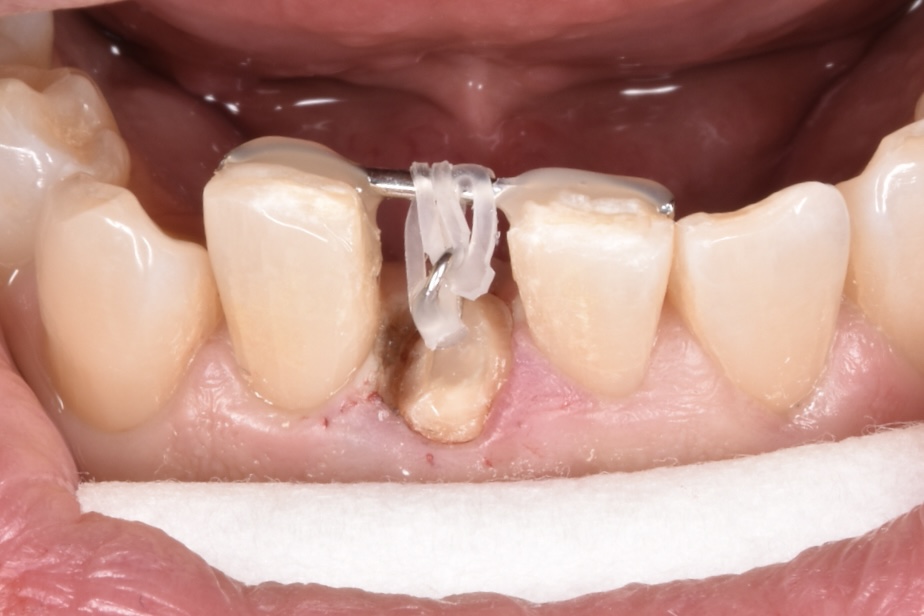

左右両隣は歯に1ミリの鋼線を使用して矯正用のゴムで折れてしまった歯を牽引しているところです。

仮の歯を貼り付けて初回の治療は終了です。

裏側はこんな感じです。舌感は悪いですが、しばしの辛抱です。汚れが溜まりやすいので衛生面には注意が必要なのと、仮歯は張り付いているだけなので、とても取れやすいです。